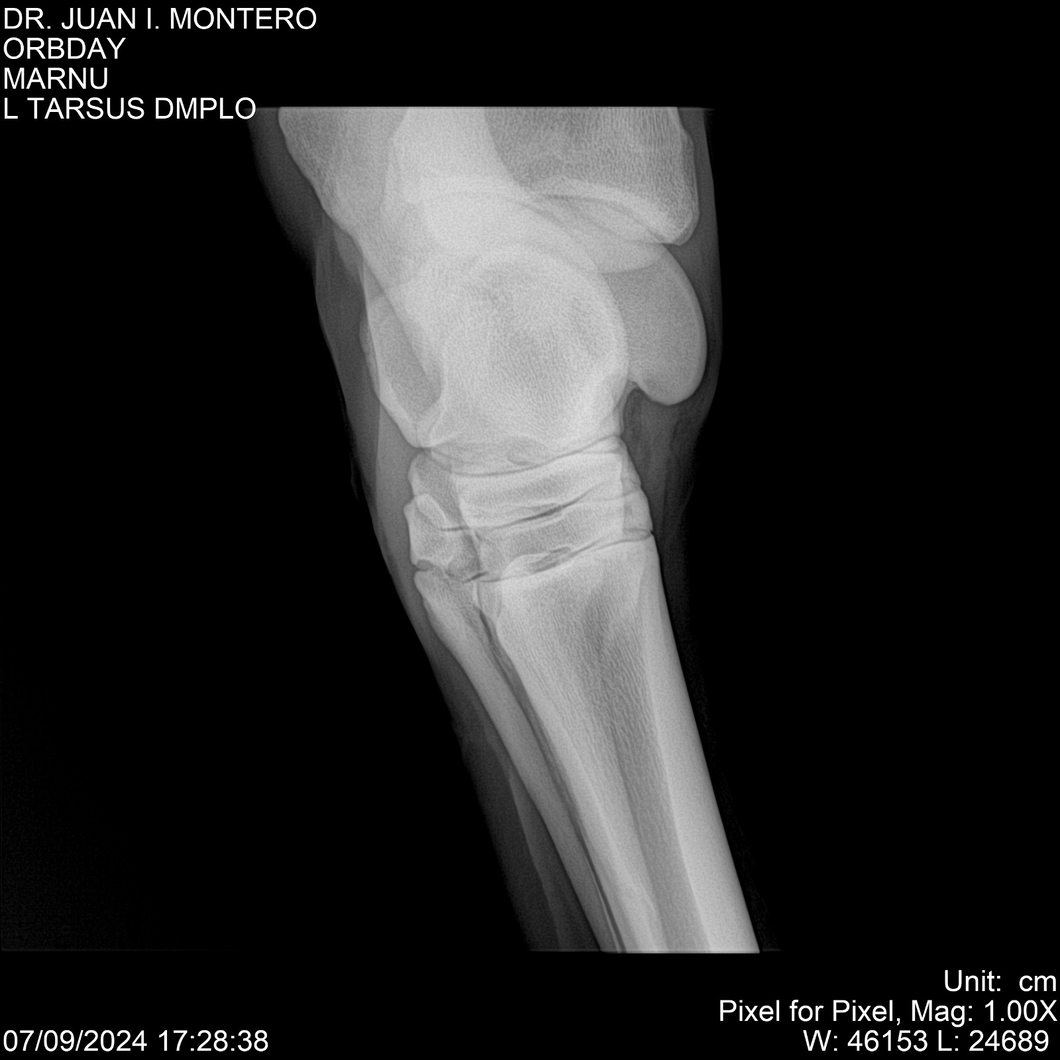

• Empresa: Abelenda N. R., Walter Hugo